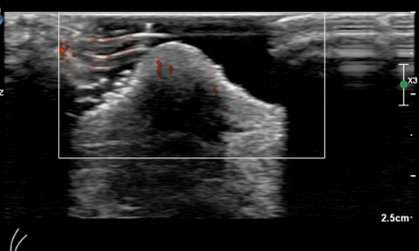

As Paget’s disease of the breast may be multicentric, it is essential to evaluate the entirety of the breast outside of the nipple/areola region to assess for additional sites of tumor. Mammogram findings of Paget’s disease of the breast include thickening of the skin at the nipple and areola, nipple retraction/inversion, microcalcifications, masses, or architectural distortion. However, a mammographic correlate may not always be seen. Ultrasound is often helpful for further evaluation when the mammogram is negative or when patients complain of a palpable lump. Ultrasound findings may include skin thickening of the nipple, heterogenous hypoechoic areas, areas of increased vascularity, discrete masses, and dilated ducts.